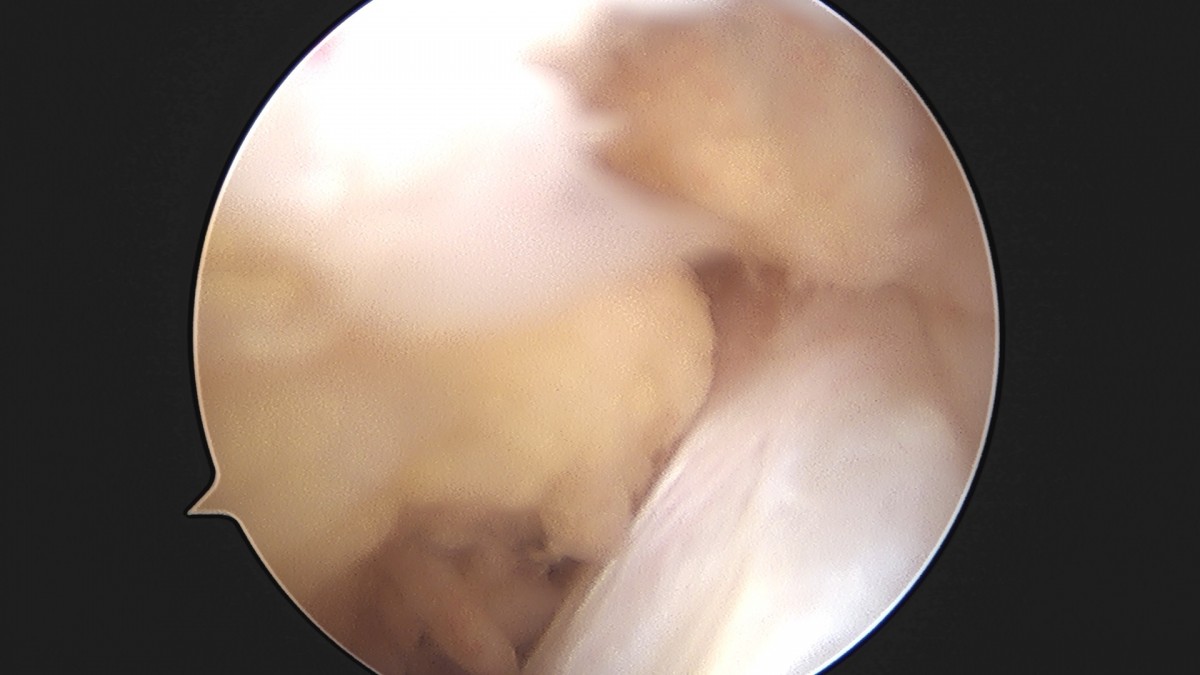

이재상원장님 무릎 반월상 연골판 절제술 박민O 환자

작성자 최고관리자 댓글 0건 조회 382회 작성일 25-09-16 15:46